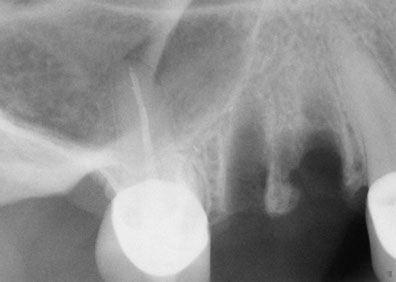

A quick and safe solution to facilitate the installation of dental implantsIn 1960, it was Philip Boyne who first used the Caldwell-Luc procedure to correct the lack of maxillomandibular space by raising the sinus membrane in the area of the molars and premolars and placing a graft composed of particulate or autogenous corticocancellous bone (originating from the patient) at the base of the to fill the bone cavity. With the arrival of titanium root implants, it was discovered that many people’s upper maxillary bones were inadequate in height and bone width, requiring a bone graft in the maxillary sinus to make them suitable recipients of for dental implants. A sinus lift is a surgical procedure that is necessary when there is insufficient bone, during which bone is added in between the upper maxilla and the maxillary sinuses, which are an annex to the nasal passages. Found on both sides of the nose, the shape and size the maxillary sinus varies in each person and with the passage of time it becomes larger (inappropriate for dental implants).

Who is a candidate for this technique?This technique is recommended in cases where it is impossible to place dental implants with the proper length required in the posterior upper jaw bone. In this area there is usually a type III or IV bone quality and because of this, it is necessary to use an implant with a minimum length of 10mm and the largest possible diameter.

The elevation of the maxillary sinus is one of the most versatile surgical implant techniques to allow the placement of dental implants.